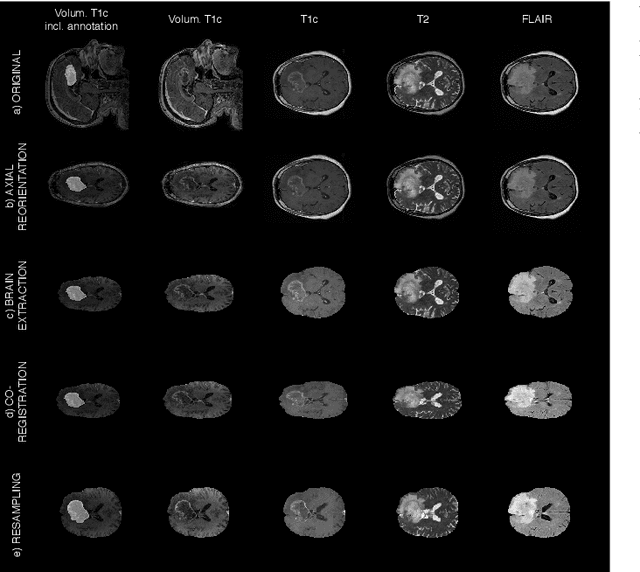

Abstract:Gliomas are the most common malignant brain tumors that are treated with chemoradiotherapy and surgery. Magnetic Resonance Imaging (MRI) is used by radiotherapists to manually segment brain lesions and to observe their development throughout the therapy. The manual image segmentation process is time-consuming and results tend to vary among different human raters. Therefore, there is a substantial demand for automatic image segmentation algorithms that produce a reliable and accurate segmentation of various brain tissue types. Recent advances in deep learning have led to convolutional neural network architectures that excel at various visual recognition tasks. They have been successfully applied to the medical context including medical image segmentation. In particular, fully convolutional networks (FCNs) such as the U-Net produce state-of-the-art results in the automatic segmentation of brain tumors. MRI brain scans are volumetric and exist in various co-registered modalities that serve as input channels for these FCN architectures. Training algorithms for brain tumor segmentation on this complex input requires large amounts of computational resources and is prone to overfitting. In this work, we construct FCNs with pretrained convolutional encoders. We show that we can stabilize the training process this way and produce more robust predictions. We evaluate our methods on publicly available data as well as on a privately acquired clinical dataset. We also show that the impact of pretraining is even higher for predictions on the clinical data.